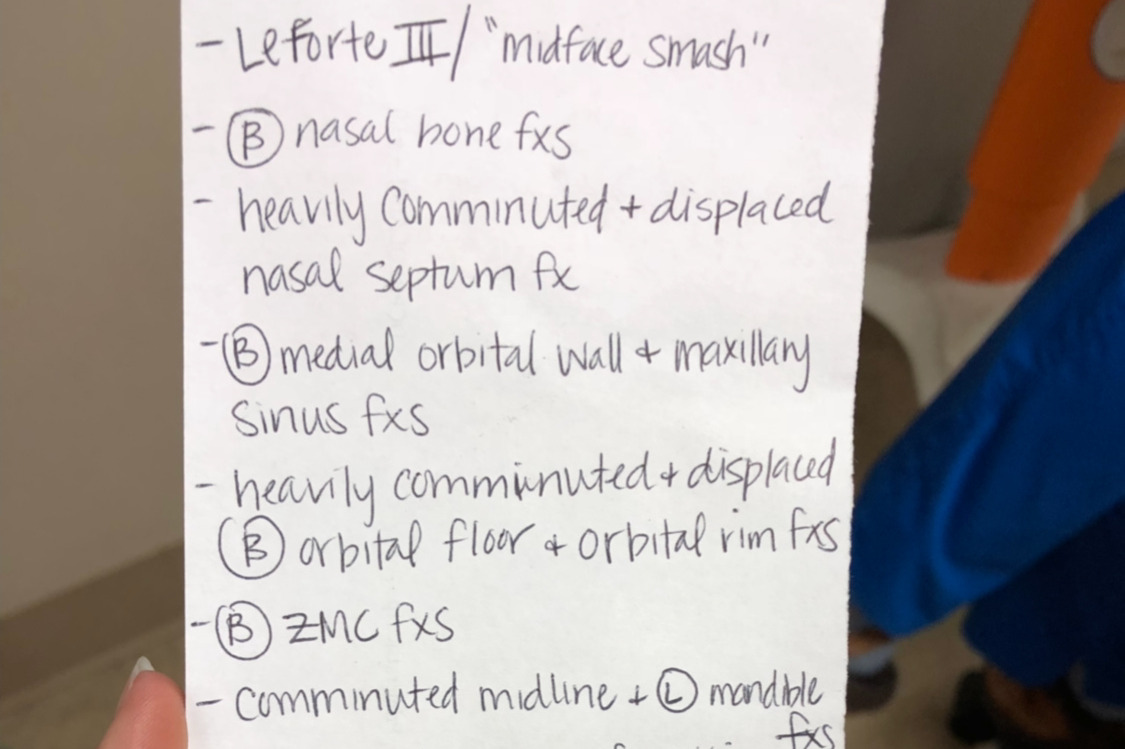

That evening, he went back for a 6-7 hour surgery. Here is a list that one of the nurses gave me that lists all of the bones that were broken. Little did we know, but this was just the beginning. Currently, he is still awaiting a bone grant surgery and dental implants. Ruled as cosmetic and a surgery that will NOT be covered by insurance. It comes to a total of approximately $32,000 for the upcoming surgery alone.

That evening, he went back for a 6-7 hour surgery. Here is a list that one of the nurses gave me that lists all of the bones that were broken. Little did we know, but this was just the beginning. Currently, he is still awaiting a bone grant surgery and dental implants. Ruled as cosmetic and a surgery that will NOT be covered by insurance. It comes to a total of approximately $32,000 for the upcoming surgery alone.